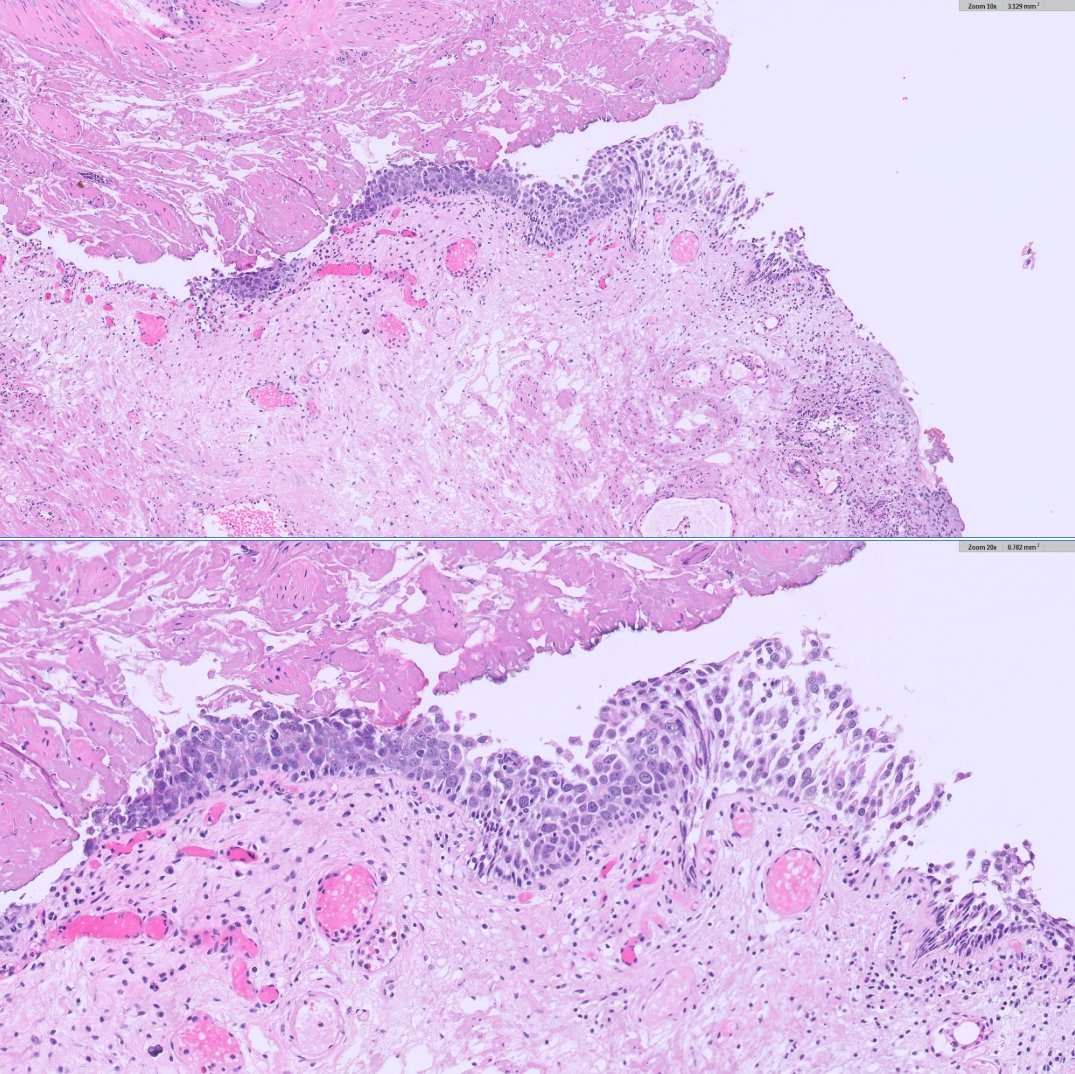

Classic histology snapshot: bladder mucosa packed with inflammatory cells surrounding characteristic schistosome eggs. A striking reminder of how parasitic infections like schistosomiasis can drive chronic inflammation and long-term complications in the urinary tract. #GUpath